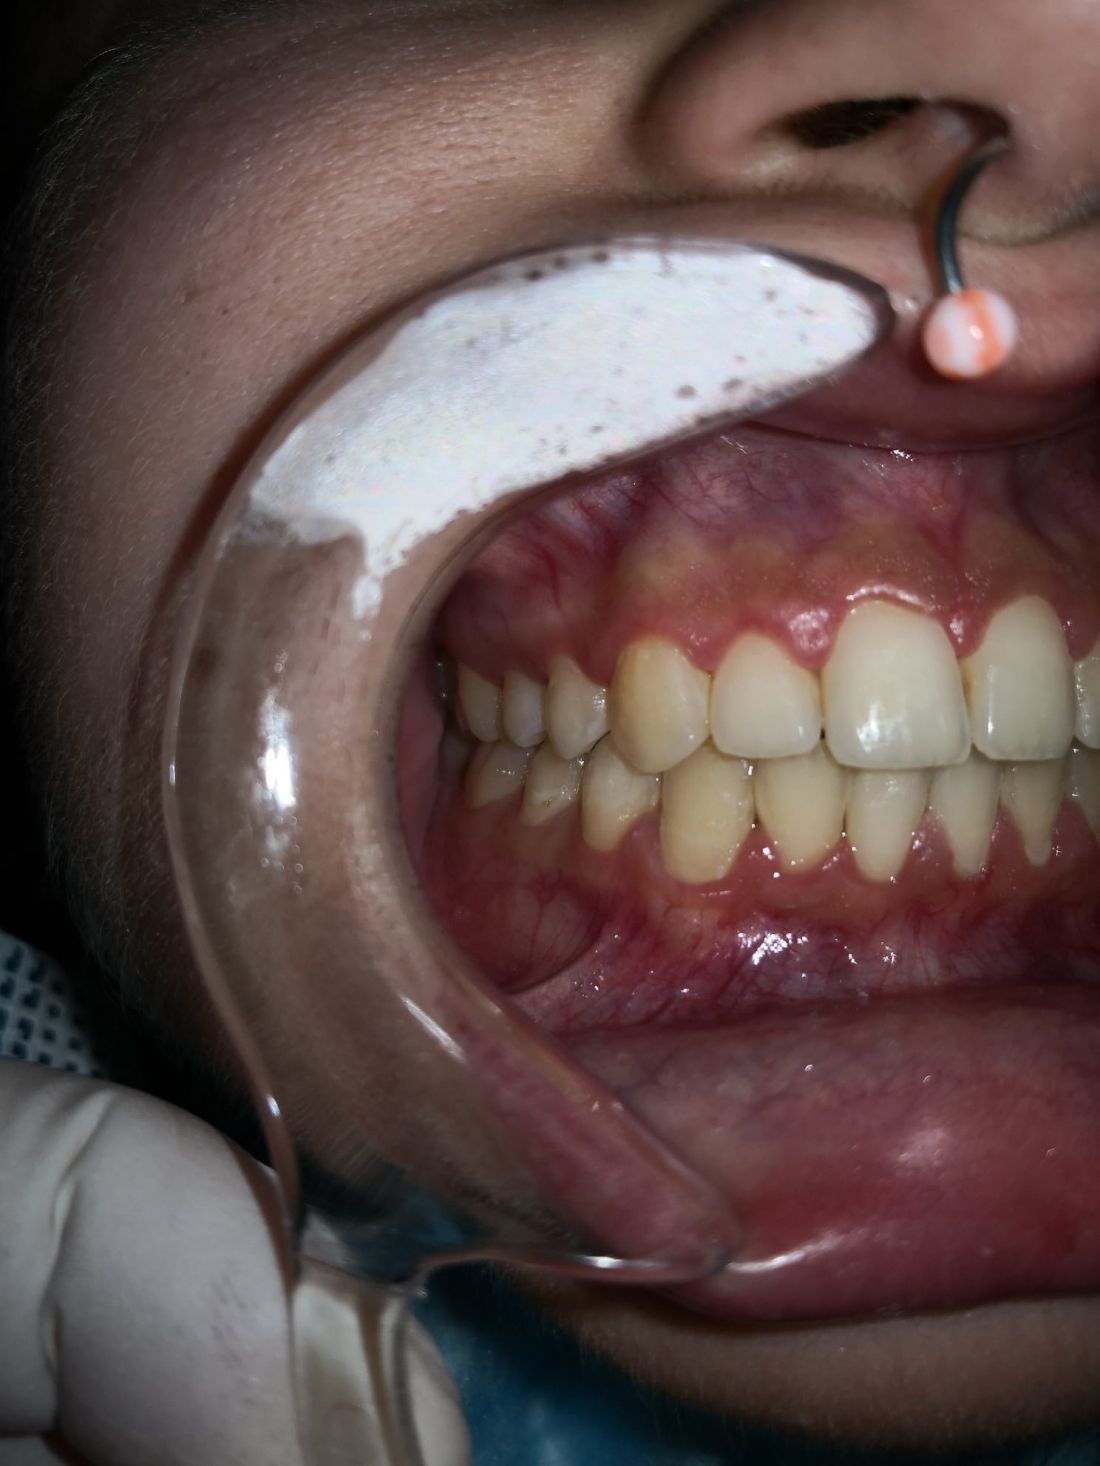

Ortopedia ortodoncia transposición